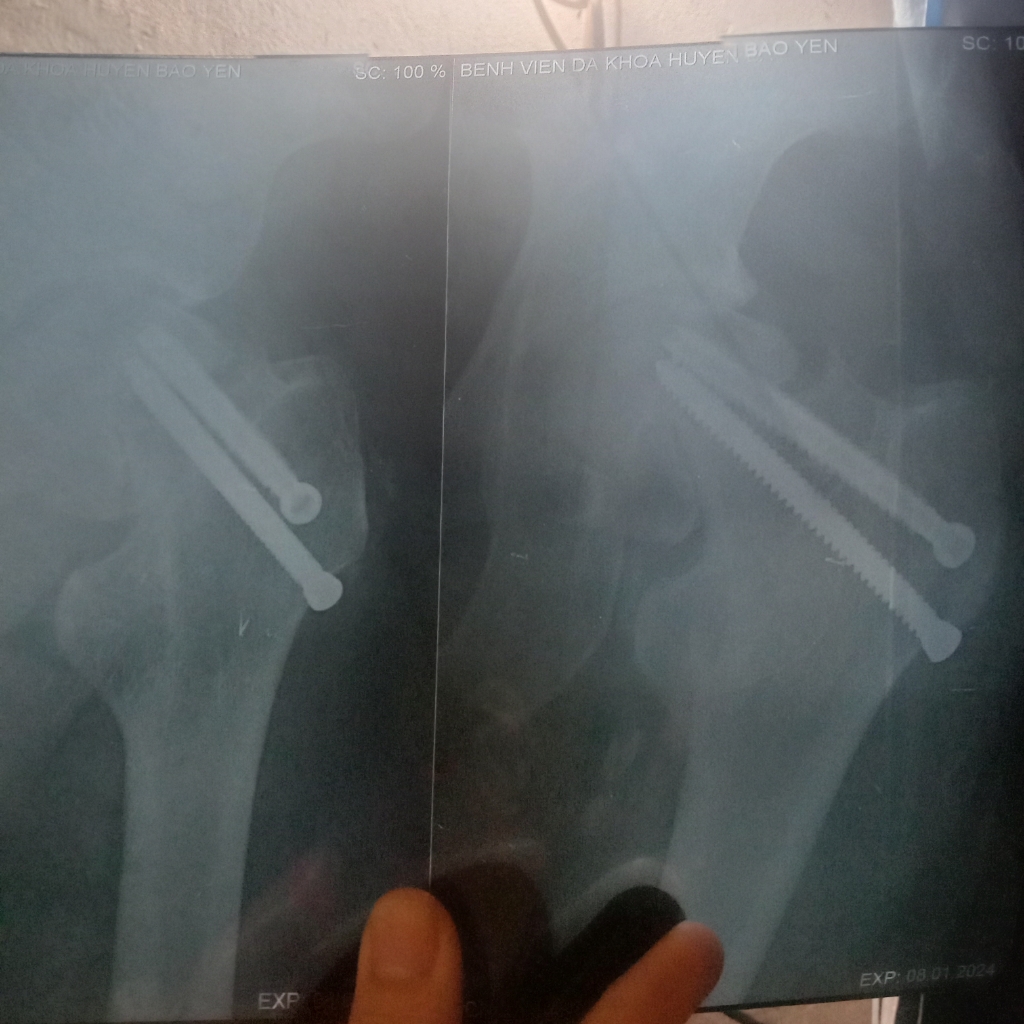

Đây là hình ảnh vít đinh của em ạ. Em thấy nó lệch lệch hay sao ạ bác sĩ.

Dương Thị Hạnh

Đinh này bs chẩn đoán hình ảnh sẽ giải thích em rõ hơn